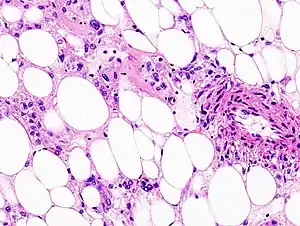

Histopathologic image of renal angiomyolipoma. Nephrectomy specimen. H&E stain.

Establishing the malignant potential of these tumours remains challenging although criteria[3] have been suggested; some PEComas display malignant features whereas others can cautiously be labeled as having 'uncertain malignant potential'.[2] The most common tumours in the PEComa family are renal angiomyolipoma and pulmonary lymphangioleiomyomatosis, both of which are more common in patients with tuberous sclerosis complex. The genes responsible for this multi-system genetic disease have also been implicated in other PEComas.[2]

PECs consist of perivascular epithelioid cells with a clear/granular cytoplasm and central round nucleus without prominent nucleoli.